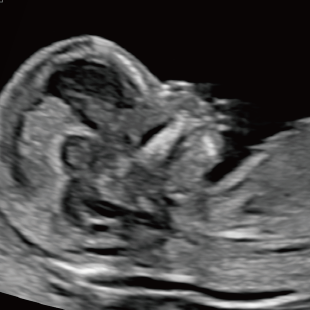

初期スクリーニングでは、首の後ろのむくみ(Nuchal translucency: NT)や鼻の骨、心臓まわりの血流などを確認し、胎児の体の特徴や発育の様子を丁寧に観察します。 これらの所見は、染色体数の変化と関連することがある特徴として知られており、21トリソミー/18トリソミー/13トリソミーなどの染色体変化の可能性を評価する指標となります。(本検査のみで確定診断はできません) また観察可能な範囲において脳や脊椎、心臓、消化管、手足などに大きな形態の変化がないかについても確認を行います。

胎児ドックの様子_初期 胎児ドックの様子_初期 胎児ドックの様子_初期 胎児ドックの様子_初期 胎児ドックの様子_初期 胎児ドックの様子_初期 胎児ドックの様子_初期 胎児ドックの様子_初期